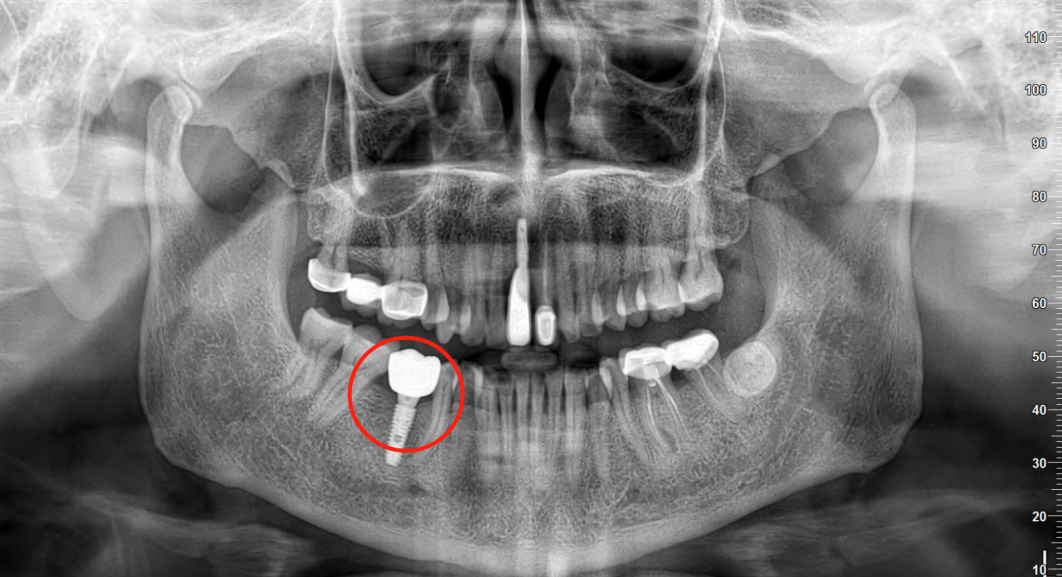

🔎种植牙

X光拍片为什么要等看牙为什么要拍片?非专业人士如何看懂自己的牙片!_https://www.jmylbn.com_新闻资讯_第11张

△种植牙等修复体在全景片上通常呈现白色。